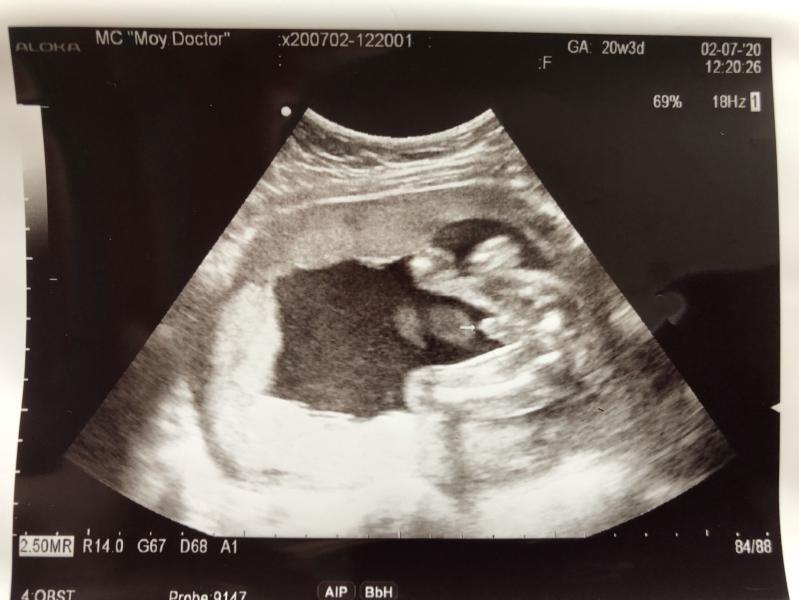

Ну здравствуй, Сыночек 👋🏼😍#второйскрининг#👶🏼#мойсыночек#ждемнашукроху🥰

Да, это прям первый кадр, который мы увидели, как допплер приложили... Сразу все стало ясно)